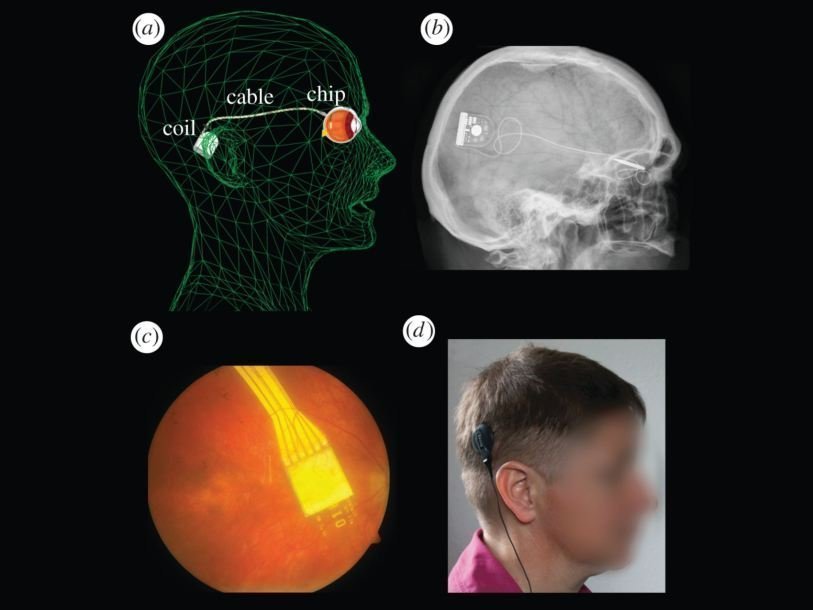

В феврале ученые из Тюбингена сообщили, что созданный ими микрочип Alpha IMS позволил вернуть зрение девяти слепым пациентам, страдающим пигментным ретинитом – наследственным заболеванием, ведущим к дегенерации клеток сетчатки и слепоте. Вживляемый под сетчатку чип, размером три на три миллиметра, при помощи фотодиодов регистрирует попадающий на сетчатку свет и передает сигнал на зрительный нерв. Пациент при помощи беспроводного пульта регулирует яркость и контрастность изображения. Правда, вернувшееся зрение позволяет видеть мир лишь черно-белым. Испытания микрочипа проходили в офтальмологических больницах Оксфордского университета и Королевского колледжа в Лондоне. Среди участников был спортсмен-параолимпиец Тим Рэддиш, который теперь смог увидеть свои 23 золотые медали. Сейчас испытания Alpha IMS продолжаются в Великобритании и Гонкоге. Другое устройство, предназначенное для помощи людям с пигментным ретинитом, начали применять в США. Оно представляет собой очки с видеокамерой и процессор, передающий сигнал на зрительный нерв.